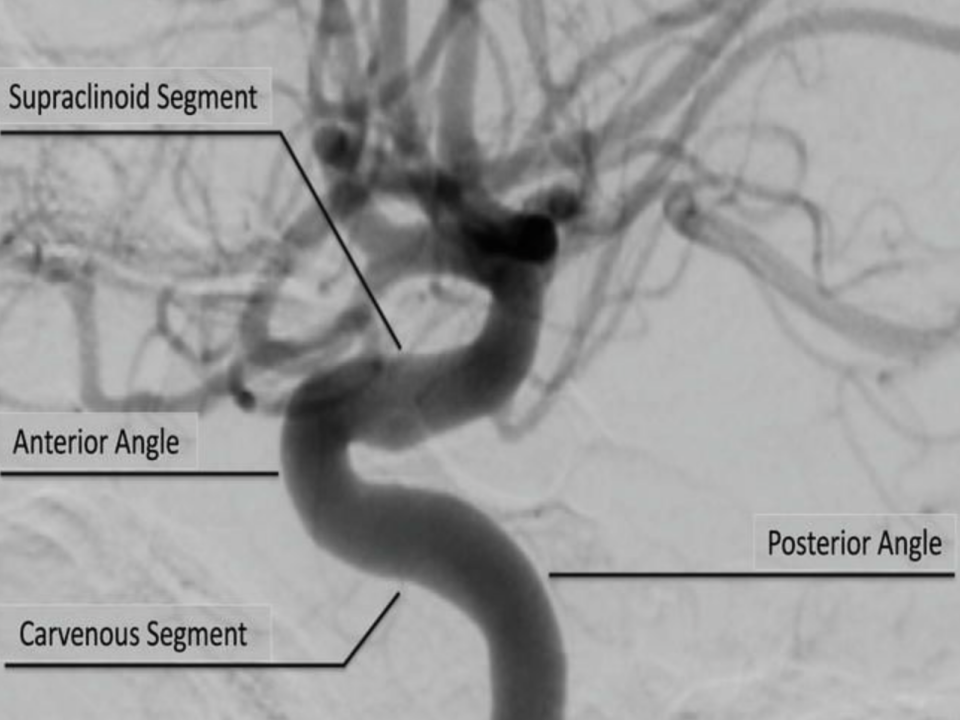

2)颈内动脉虹吸部(SCA)

颈内动脉(ICA)经颈动脉管进入颅内后在海绵窦内向前上行,经前床突最后到达颅内终末段。通常根据ICA在颅内走向,我们可以检测到正向的海绵窦段(C4),膝部为双向血流频谱(C3段),床突上段(C2段)为负向血流频谱。

方法:首先在眼窗获得OA的血流信号,通过增加取样容积深度为55-75mm,声束向内下或内上,分别获得C4段和C2段血流频谱。